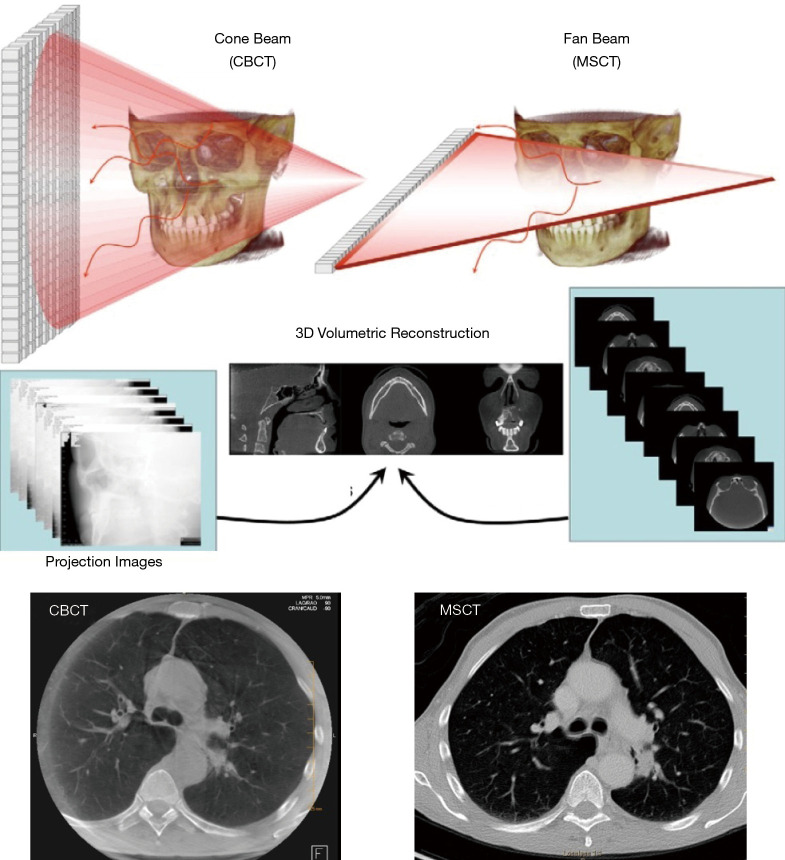

Figure 3.

Comparison of cone beam (CBCT) and fan beam (or Multi Slice CT) acquisitions. On the left, in cone beam, 2D projection images are generated as the C-arm rotates around a stationary patient, which are then reconstructed into a 3D image volume. On the right, in fan beam, X-rays are emitted in a thin fan-beam geometry and detected by a 1D array in a helical pattern as the patient table moves through the scanner. Axial slices are reconstructed, which can be reviewed as a 3D image volume. Bottom figures depict matched CBCT and MSCT chest images from the same patient. Figure adapted from reference (18), with permission. CBCT, cone beam computed tomography; MSCT, multi slice computed tomography.

In general, CBCT is commercially available as an interventional imaging modality which is not intended for diagnostic use. CBCT and MSCT images have similar spatial resolution, but CBCT has reduced contrast resolution, making it more difficult to discriminate among soft tissues. In addition, image intensity with CBCT is non-calibrated gray scale values, as opposed to the calibrated Hounsfield Units (HU) used in MSCT. Thus, a standardized lung window, as is used with MSCT, is not possible with CBCT. Despite these differences in image appearance, the ability to use CBCT for intraprocedural guidance is an important advantage for bronchoscopic procedures.

From the practical standpoint, the main disadvantages of MSCT when compared with CBCT are that the head of the patient is typically inside the gantry (making bronchoscopy technically challenging) and the fact that the patient moves during the scan, and this movement can dislodge our bronchoscopy tools losing contact with the target.